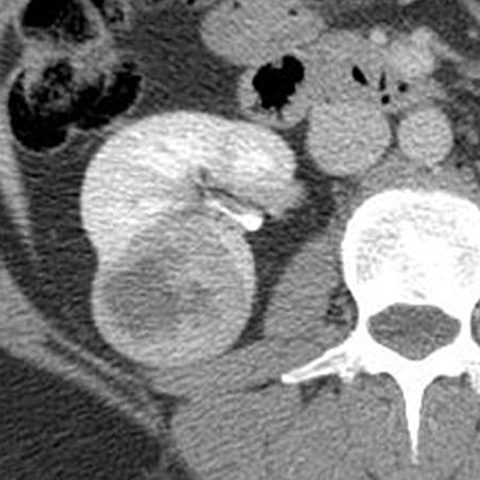

67-year-old male with flank mass and hematuria [2 of 3]